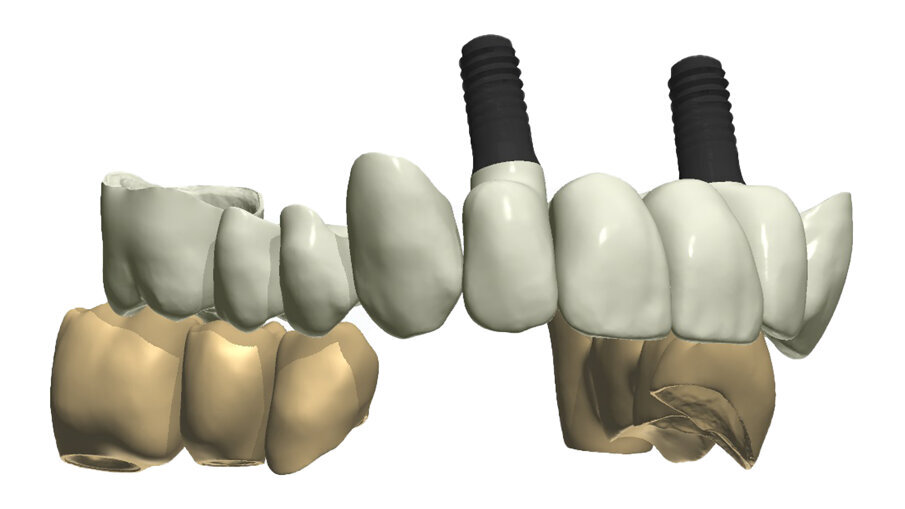

Gli impianti in Zirconia non offrono molte soluzioni protesiche, è importante che il loro posizionamento tenga conto di quest’aspetto mettendo l’odontotecnico nelle condizioni più favorevoli (Fig. 38). Questa sistematica prevede l’uso di un moncone in titanio cementato nella struttura protesica che permette l’avvitamento all’interno dell’impianto. Nella connessione implantare è presente un’intercapedine dove alloggia il collarino in titanio del T-base totalmente inglobato all’interno della zirconia, evitando comunicazioni coi tessuti adiacenti. Va comunque considerato l’aspetto tecnico importante legato allo spessore della struttura in zirconia che deve avvolgere l’intero moncone in titanio. (Fig. 39, 40).

Fig. 38_Il ponte tra gli impianti in Zirconia rappresenta un progetto complesso tra il rispetto del tunnel mucoso, l’anatomia vestibolare, gli spazi circolari e il foro per l’avvitamento coronale.

Fig. 21_Il posizionamento non prevede l’uso della dima e in quest’immagine si evidenzia il livello d’inserimento che ha tenuto presente il livello crestale palatale, i mounter evidenziano il parallelismo ottenuto grazie al meticoloso lavoro sommato alla conoscenza della tecnica chirurgica.